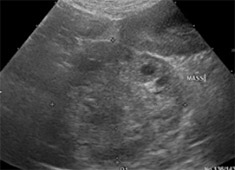

検査:腹部超音波検査にて肝臓内側右葉に直径約12cm大の肝臓腫瘍が認められました。また、胆のうに重度の胆泥の貯留を認めました。

治療:飼い主様の希望により、肝臓腫瘍摘出手術と胆嚢切除手術行いました。肝臓腫瘍摘出は特に血管系の処理が重要で基本的な結紮技術はもちろん、超音波乳化吸引装置や血管シーリング装置などを駆使し血管を一つずつ処理して行きます。

肝臓腫瘍と胆嚢を摘出した写真です。肝臓腫瘍摘出には超音波乳化吸引装置を使用し、かなり安全に手術が可能でした。

胆嚢内にはゼリー状の内容物が詰まっていました。手術後は2日後から食欲も改善し、状態も改善しました。病理検査で肝細胞癌との診断でしたが、手術で切除しきれているとのことで、今後は無治療で経過観察中です。